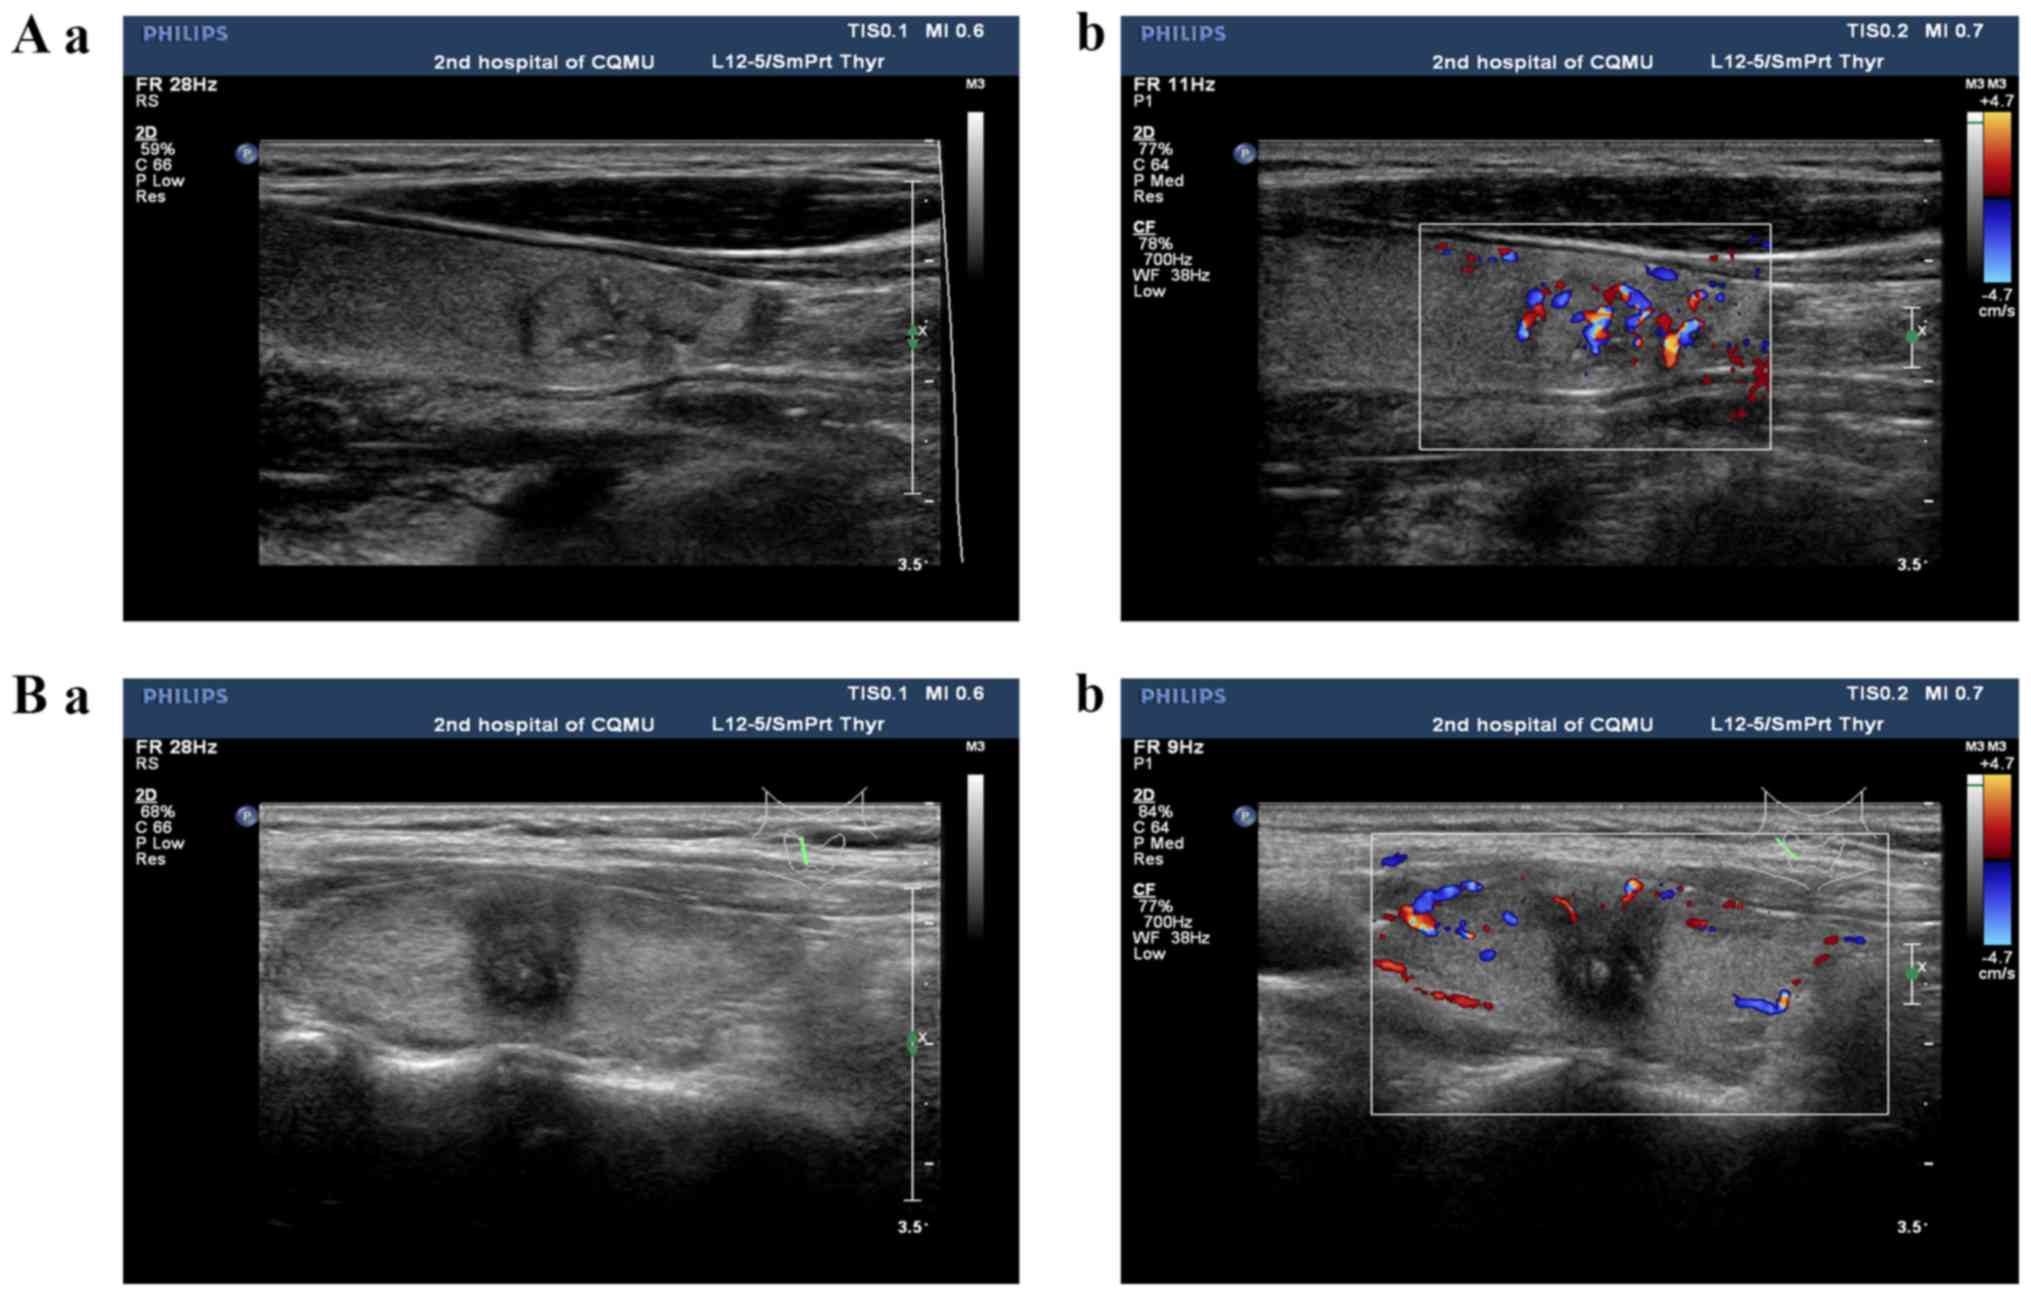

Frontiers Differentiation Of Thyroid Nodules Difficult To Diagnose With Contrast Enhanced Ultrasonography And Real Time Elastography

Benign And Suspicious Ultrasound Features And Pathological Findings He Download Scientific Diagram

Role Of Ultrasound Color Doppler Elastography And Micropure Imaging In Differentiation Between Benign And Malignant Thyroid Nodules Sciencedirect